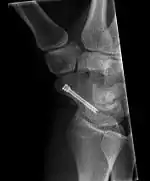

Scaphoid fracture before and after operation

Fractures of the scaphoid are the most common of the carpal bone injuries, because of its connections with the two rows of carpal bones.[1]:177

The scaphoid can be slow to heal because of the limited circulation to the bone. Fractures of the scaphoid must be recognized and treated quickly, as prompt treatment by immobilization or surgical fixation increases the likelihood of the bone healing in anatomic alignment, thus avoiding mal-union or non-union.[5] Delays may compromise healing. Failure of the fracture to heal ("non-union") will lead to post-traumatic osteoarthritis of the carpus.[1]:189 One reason for this is because of the "tenuous" blood supply to the proximal segment.[2] Even rapidly immobilized fractures may require surgical treatment, including use of a headless compression screw such as the Herbert screw to bind the two halves together.

Healing of the fracture with a non-anatomic deformity (frequently, a volar flexed "humpback") can also lead to post-traumatic arthritis. Non-unions can result in loss of blood supply to the proximal pole, which can result in avascular necrosis of the proximal segment.

Scaphoid fractures may be difficult to diagnose via plain x-ray. A repeat x-ray may be required at a later date, as might cross-sectional imaging via MRI or CT scan.[5]